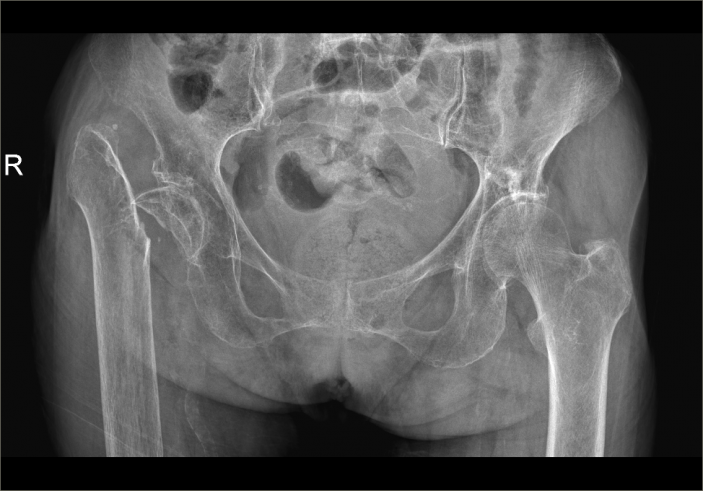

經過CT檢查發現老人家的左股骨頸骨折。此外還伴有老年性骨質疏松、高血壓病、低鈉低鉀血症等疾病。骨科吳志斌主任随即請内科、麻醉科專家會診。予監控血壓、血糖,抗骨質疏松、營養心肌等對症治療。待患者病情穩定、可耐受手術後進行手術治療。

△術前